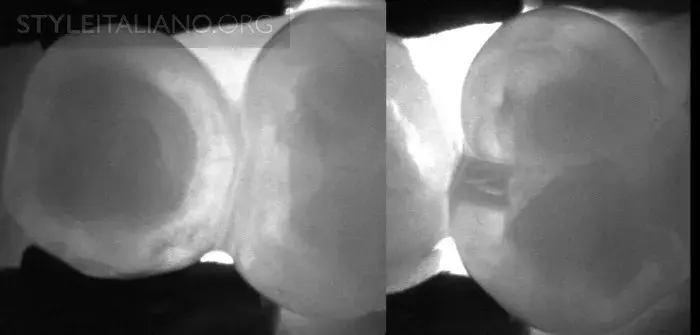

Рис. 8 – Фиссура - одна из анатомически сложнейших областей зуба. Мы можем получить представление о происходящих в ней процессах - фиссурном кариесе.

Рис. 9 – Предварительная рентгенограмма. Скрытый кариес: кариес дентина на окклюзионной поверхности. Деминерализация достаточно большая, чтобы обнаружить ее с помощью просвечивания.

Рис. 16 – Просвечивание зубов показывает полости в истинном размере, а на рентгене они уменьшены.

Рис. 17 – Рентген слева, просвечивание справа.